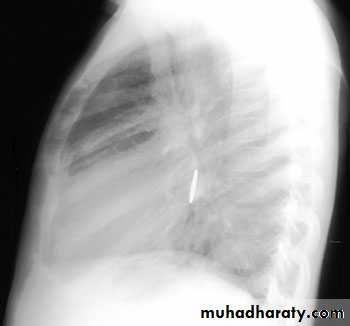

CXR : expiratory or lateral decubitus , reveal the presence of radiopaque objects and can also identify focal air trapping.

Expiratory chest radiograph in a 12-month-old boy with a 2-month history of wheezing demonstrates continued hyperlucency and hyperexpansion of the right hemithorax.